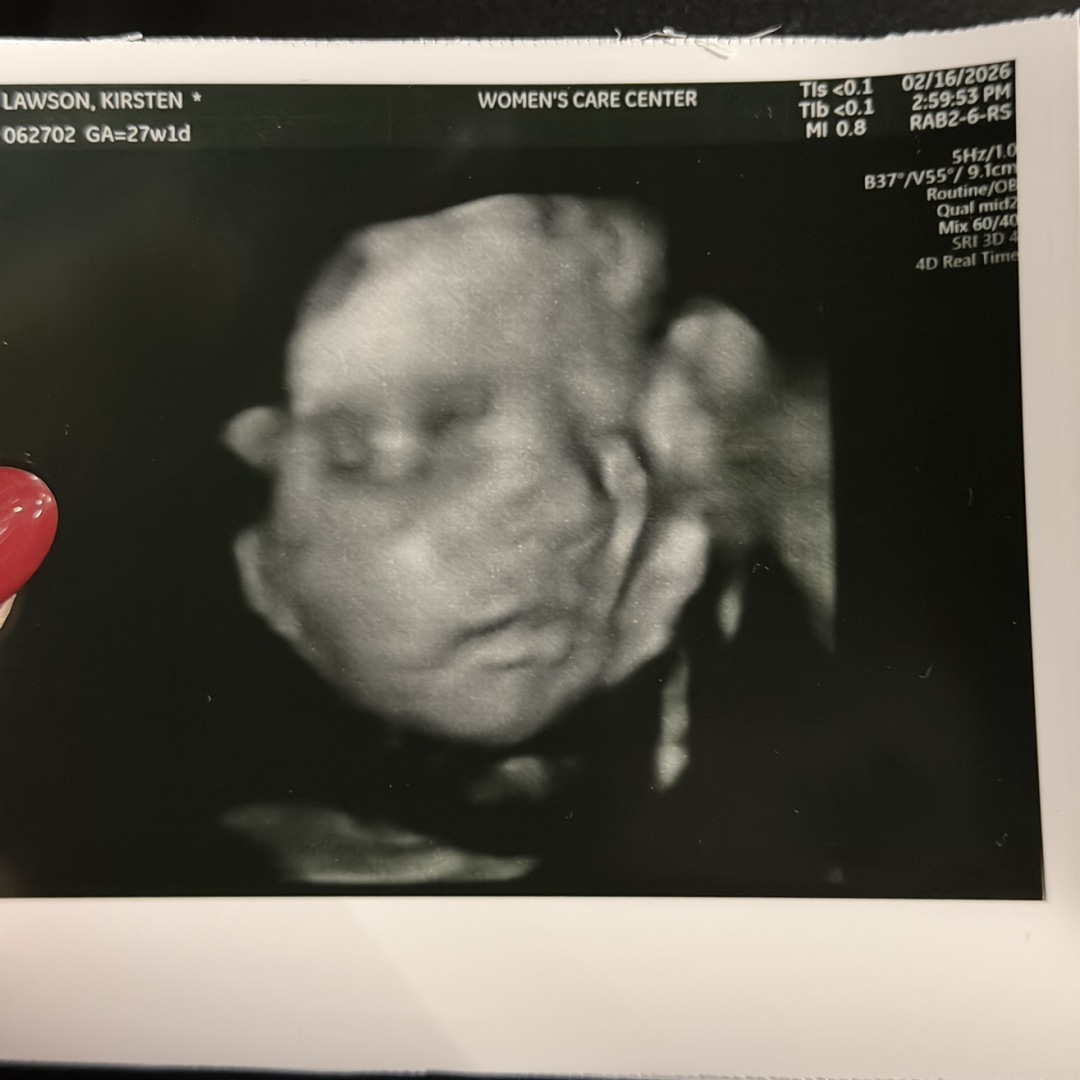

Baby Noah’s Registry

Kirsten Lawson

Zoe, KY

May 17, 2026